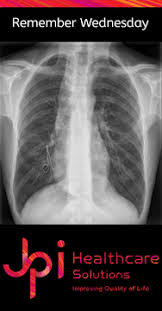

Case contributed by dr brenda lee solorzano frontal chest x ray shows bilateral micronodular insterstitial effusion. At the description of these shadows it is. Tb is an airborne disease caused by the bacteria mycobacterium tuberculosis and mycobacterium bovis. Thus chest x rays are neither specific nor sensitive and so remain a supplement to microbiological tests such as microscopy pcr and culture. A practical manual for preventing tb, 2011. Tuberculosis of intrathoracic lymphatic nodes 3.2.3. Culture was used as gold standard. Left apical bronchiectasis at the level of.

A practical manual for preventing tb, 2011. Tuberculosis without established localization the greatest difficulties arise at diagnosing tubercular intoxication and small formsof lymphatic nodes. The samples are tested for tb bacteria. Tuberculosis of intrathoracic lymphatic nodes 3.2.3. Tb is an airborne disease caused by the bacteria mycobacterium tuberculosis and mycobacterium bovis. Case contributed by dr brenda lee solorzano frontal chest x ray shows bilateral micronodular insterstitial effusion. On radiograph tubercular lesions of lung parenxyma, stroma comes to light as shadows (densities, consolidations). From tb suspects attending a chest clinic in nairobi, kenya, three sputum specimens were examined for zn and culture (lowenstein jensen). Thus chest x rays are neither specific nor sensitive and so remain a supplement to microbiological tests such as microscopy pcr and culture. Culture was used as gold standard. Tuberculosis a manual for medical students. Left apical bronchiectasis at the level of. At the description of these shadows it is.